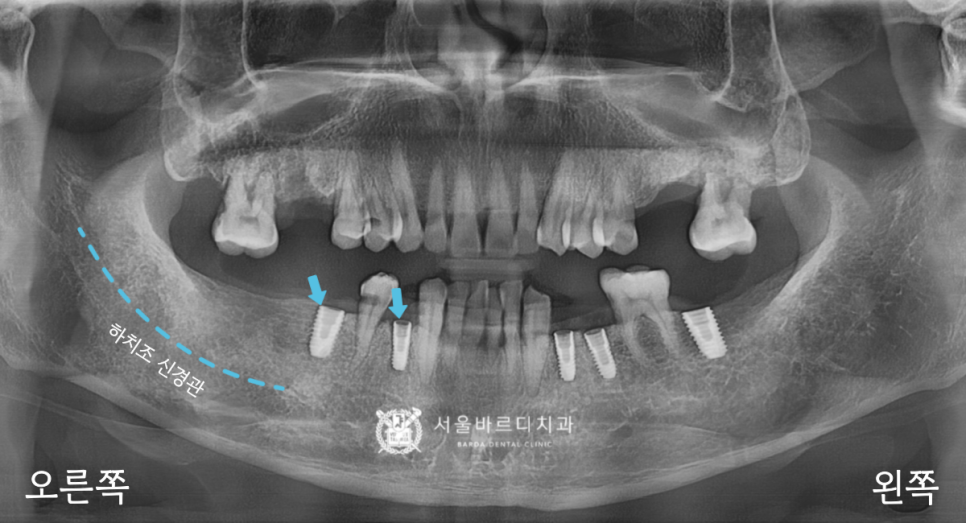

가이드 장치를 끼운 상태에서

해당 부위만 길을 만들어서 픽스처를 심은 덕분에

하치조 신경관의 손상 없이 바르게 심겼네요.

20230223

만약에 신경관을 건드리게 된다면

입술이나 볼에 마취가 안 풀린 것처럼

둔한 감각이 남아있어서 신경이 돌아올 때까지

별도의 치료가 필요하게 되는데요.

이를 막기 위해서 CT를 분석하여

미리 계획해둔 자리에 심은 덕분에

오른쪽도 손상 없이 안전하게 들어갔습니다.